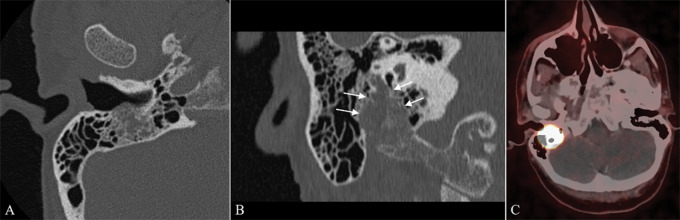

We report the case of a 54‑year‑old woman with 3‑year‑history of right facial paralysis. Computed tomography (CT) and magnetic resonance imaging (MRI) findings were highly suggestive of a primary paraganglioma (PGL) of the facial nerve canal (FNC). 68Ga‑DOTATATE positron emission tomography (PET)/CT confirmed the neuroendocrine nature of the tumor. Teaching point: The combined imaging findings of permeative bone destruction, rapid wash‑in and wash‑out perfusion, and 68Ga‑DOTATATE tracer uptake in a lesion arising from the mastoid segment of the FNC are diagnostic of a primary PGL of the FNC and may obviate the need for histological confirmation.

我们报告一例54岁女性,有3年的右侧面瘫病史。计算机断层扫描(CT)和磁共振成像(MRI)的结果高度提示面神经管(FNC)原发性副神经节瘤(PGL)。68Ga - DOTATATE正电子发射断层扫描(PET)/CT证实了肿瘤的神经内分泌性质。教学要点:FNC乳突段病变的穿透性骨破坏、快速洗入和洗出灌注以及68Ga - DOTATATE示踪剂摄取的综合影像学表现可诊断FNC原发性PGL,可能无需组织学证实。